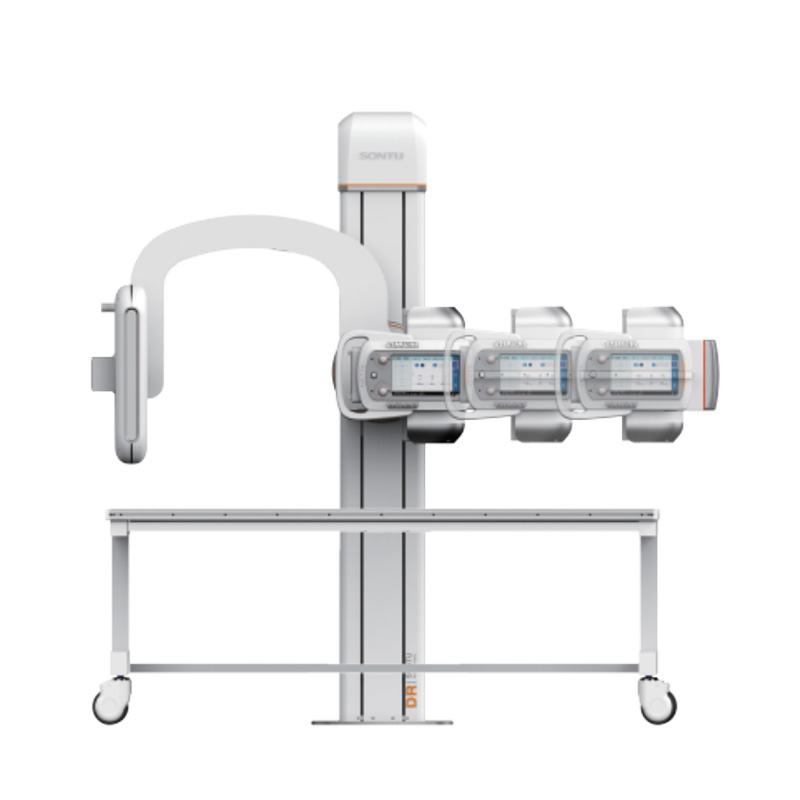

深图SONTU 数字化透视摄影X射线机

SONTU500-Sirius UC

产品优势

-

高热容量球管

高性价比球管高品质,保证球管稳定输出

-

高频高压发生器

高频高压性能稳定保障了优越的图像清晰细腻的展现

-

UC臂式机架系统

横臂旋转范围-30°~+120°,探测器旋转范围-45°~ +45°,满足更多临床拍摄需要

-

大尺寸液晶触摸屏

采用大尺寸液晶触摸屏,牛头配有人性化的前后双把手束光器与牛头一体化设计,可在牛头操作束光器

产品参数

- 平板探测器尺寸 ≥17″×17″

- 像素矩阵 ≥3072*3072

- 有效数据位数 ≥16bit

- 标称功率 ≥50kW

- 焦点功率 ≥27/75kW

- 加载时间 ≥6.3s

- 脉冲透视电流 ≥16mA

- 阳极热容量 ≥300kHu

- 管电流调节范围 10mA~630mA

- 连续透视管电流调节范围 0.5mA~10mA

- 电流时间积调节范围 0.1mAs~630mAs

- 球管阳极旋转速度 ≥9700 转/分钟(180hz)